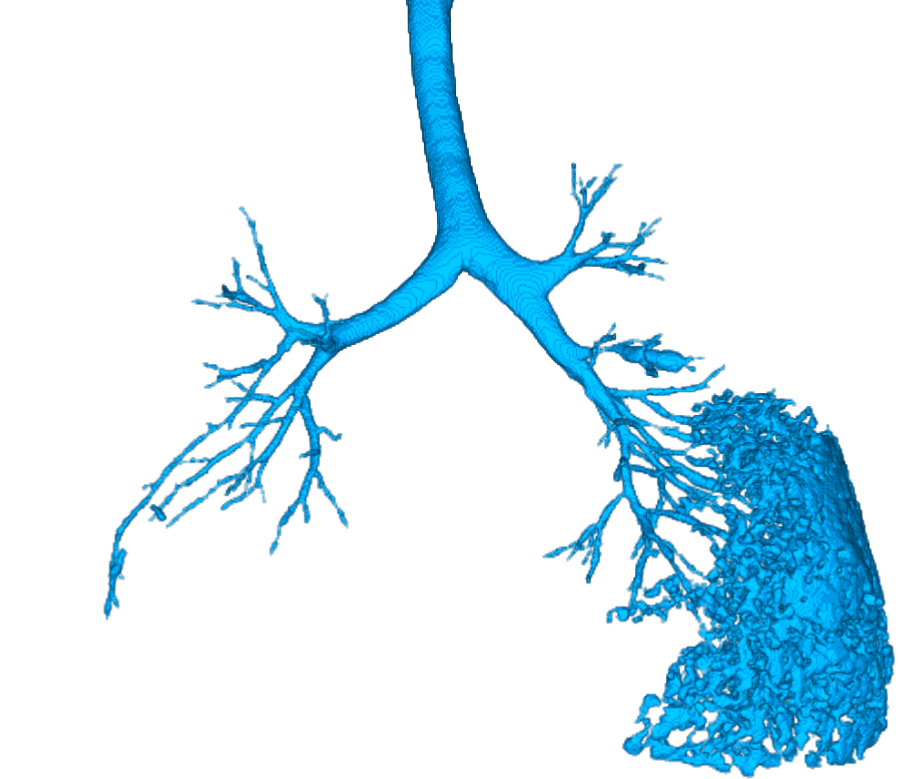

2.3 Centerline extraction

In a non-maximum suppression step inspired by [2], at each position with a medialness , we sample 8 points on a plane perpendicular to the estimated vessel direction. If the medialness on any of those 8 points is larger than at the current position , the VE response at is set to zero. This leads to disconnected vessel centerline fragments due to branching points, where the tubularity assumption fails. Next, small centerline fragments (less than 5 -connected voxels) are removed, and all maxima lying on the airway border are cleared. To reconnect the centerline fragments, we apply a Dijkstra-like shortest path algorithm. In each lung separately, we connect all centerline candidate points to the center of the heart. As a cost function, we combine the medialness with the gradient magnitudes of the CT image. The separate processing of right and left lung ensures that wrong connections through the mediastinum are avoided. The connected trees of the right and left lung form the final vessel tree.

2.4 Vessel segmentation

At each centerline voxel, 48 points lying on a sphere are sampled from the CT image and the grey values are summed up. This is done for spheres with different diameters. As soon as the normalized sum of grey values drops under 0.6 (empirically found), the radius of the vessel has been found. This gives a more accurate radius estimation compared to the filter radii directly from the VE filter response. This coarse segmentation is then used as an input for a total variation based segmentation [16], which gives the final segmentation.